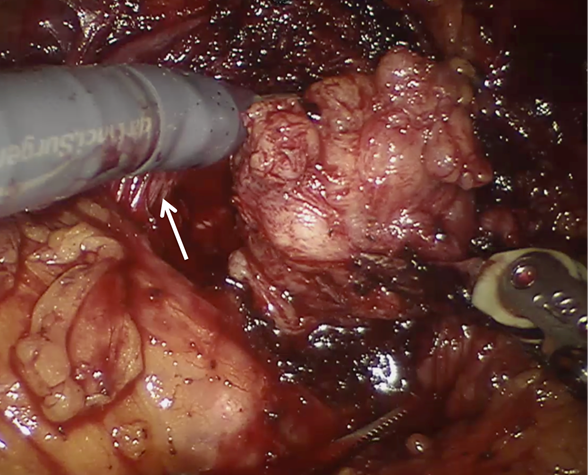

Se utiliza disección roma y cortante sobre la cápsula prostática hasta exponer la porción proximal de la uretra prostática. Se diseca para separar el adenoma prostático de la uretra. Posteriormente, se identifica el plano avascular entre el adenoma y la cápsula prostática y se lleva a cabo una disección del plano lateral y posterior para separar el adenoma de la cápsula prostática y permitir establecer un plano circunferencial alrededor del adenoma. (Figura 2) Se inicia de la base hasta el ápex prostático.

Enucleación de adenoma prostático en lóbulo derecho. Se observa uretra prostática íntegra (flecha). En este punto, la hemostasia en lecho prostático es realizada con energía monopolar y bipolar distante a la uretra para evitar lesión advertida.

Figura 2 Enucleación de adenoma prostático en lóbulo derecho